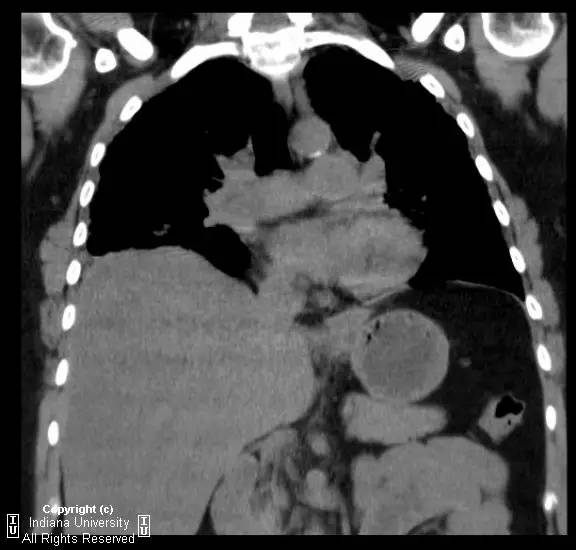

【影像学表现】胸片示双肺纹理增多,间质性透光度减低。无局灶性病变,气胸或胸腔积液。心脏及纵膈轮廓正常。CT示双肺弥漫间质性病变,累及所有肺叶,以下叶为著。肺间质增厚,结构扭曲,牵拉性支气管扩张,外周呈蜂窝状改变。肺动脉增粗,符合肺动脉高压。

【诊断】普通型间质性肺炎/特发性肺间质纤维化(活检证实)

Usual interstitialpneumonia / idiopathic pulmonary fibrosis (biopsy proven).